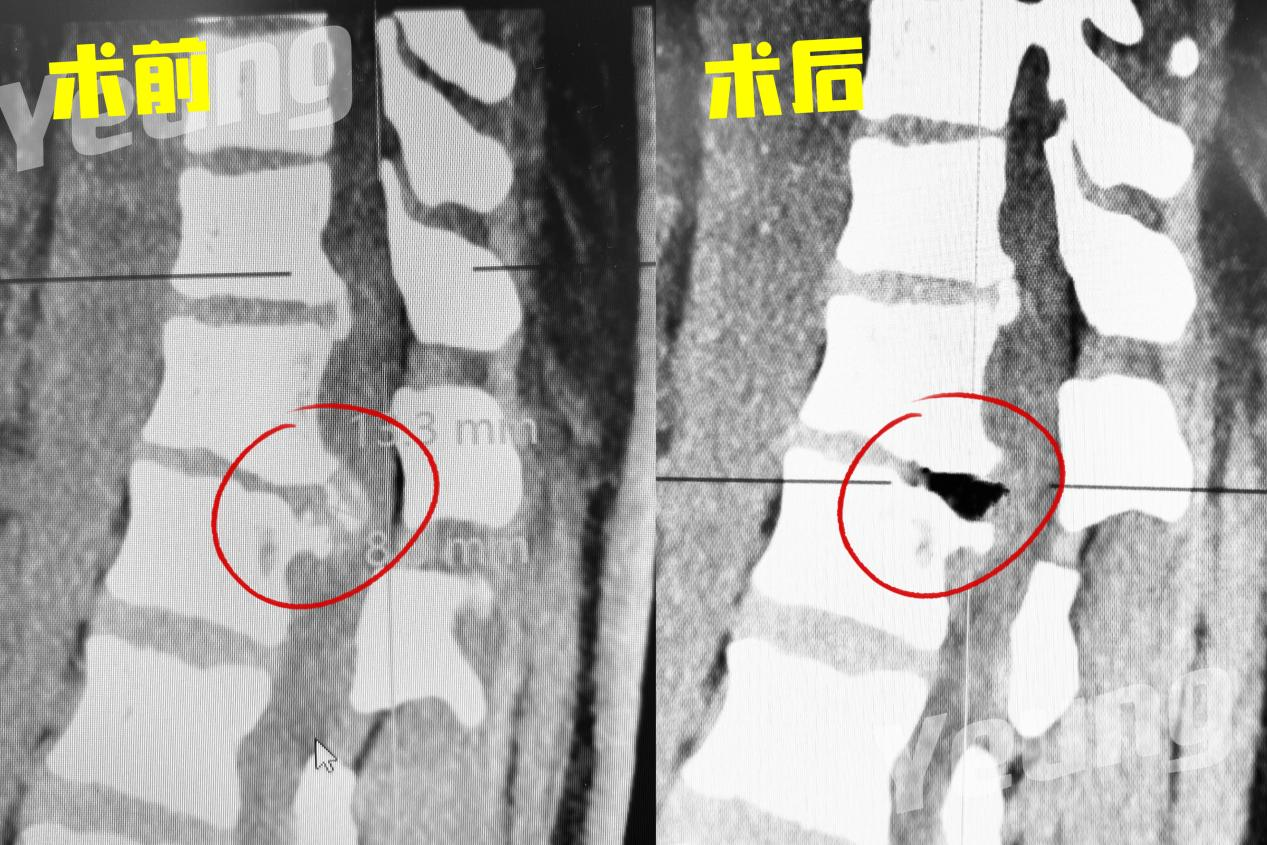

杨俊松副主任医师接诊后结合患者病史、体征和影像学资料指出,患者胸12 腰1椎间盘突出症诊断明确,双侧脊髓神经严重受压,椎间盘严重钙化。

CT显示:间盘突出&钙化严重

MRI显示:间盘突出&脊髓神经严重受压

手术中,杨俊松副主任医师在术中影像科的密切配合下采用S8导航进行了实时的操作导引,给手术插上了“透视眼”。为增加手术安全性,采用超声骨刀仔细去除钙化物,给受压的脊髓神经减压,影像显示减压彻底。

手术前后影像资料对比

本例患者术前双侧均有症状,内镜下单侧入路手术后双侧症状均缓解,且出血少,贫血患者更安全,恢复快。患者术后行走,笑容满面。